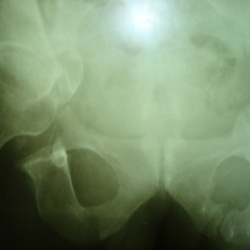

15.04.2011 - 19:03

добрый вечер. мой коллега, проводя экскреторную урографию случайно обнаружил аномалию развития костей таза: нарушение целостности тазового кольца с диастазом между лобковыми костями до 6 см. не могла...